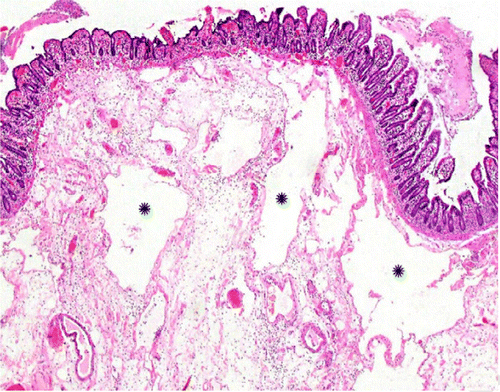

В частности, как пояснил специалист, у некоторых пациентов с COVID-19 внезапно развивался пневматоз - патологическое состояние системы пищеварения, при котором газы проникают в толщу стенки кишечника и образуют там воздушные кисты. Кроме того, у нескольких людей было выявлено необычное желтое обесцвечивание кишечника, еще у трех больных - инфаркт кишечника.

© Radiology